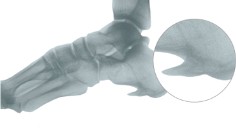

Piedi cavi

- Arco longitudinale rinforzato, accorciato, attivo e passivo, non correggibile

- Arco trasversale allargato, in molti casi appiattito, più basso del retropiede (metatarso cavo)

- Callosità nella zona dei metatasi e retropiede con sovraccarico dell’avampiede

- Piede equino e tendenza al varo dei retropiedi con possibile caduta laterale

-Dita ad artiglio contratte con calli sopra le articolazioni mediali